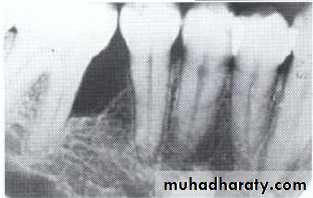

Radiographically:

Bulbous crownsCervical constriction

Thin roots

Early obliteration of roots canals & pulp chambers.

Radiographically (Type I& II ):

partial or total obliteration of pulp chambers & root canals by continued formation of dentin.

roots may be short & blunted.

Normal cementum, periodontal membrane & bone .